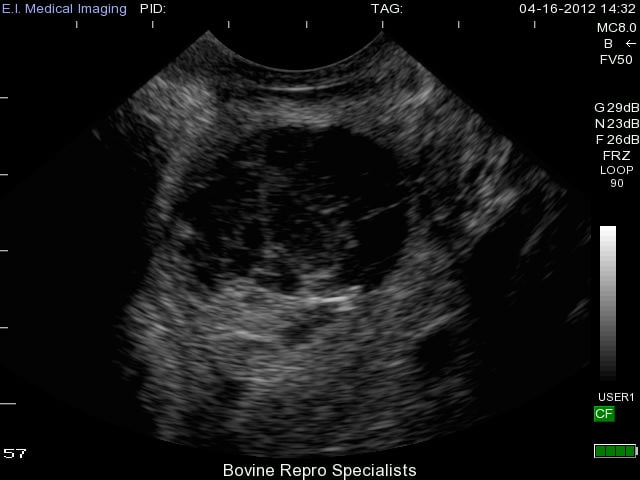

With luteal cysts originating from follicular cysts, the same mechanisms for follicular cysts development described above exist for luteal cysts. The major distinguishing factor between the two is that luteal cysts partially luteinize. Luteal cysts can also have different appearances on the ultrasound depending on the rate of luteinization. This is apparent in the next two images below depicting more examples of luteal cysts. You can see in this first image that luteinization has occurred along the bottom rim of the cyst and again the cobwebs of fibrous tissue are attempting to luteinize the rest of the cyst, but the upper portion of the lumen is still fluid-filled.

A major advantage of ultrasound when dealing with these cysts is its ability to distinguish a luteal cyst from that of a very young corpus luteum (day 5 or 6 of the estrous cycle). An early corpus luteum will also have a fluid-filled lumen and cobwebs as it continues to luteinize. Using rectal palpation, it is extremely difficult to palpate an early corpus luteum let alone distinguish it from a luteal cyst as they both have similar palpable features, but can be more clearly differentiated with an ultrasound. An early corpus luteum is depicted below and you can see the difficulties in palpating the difference between this and a luteal cyst.